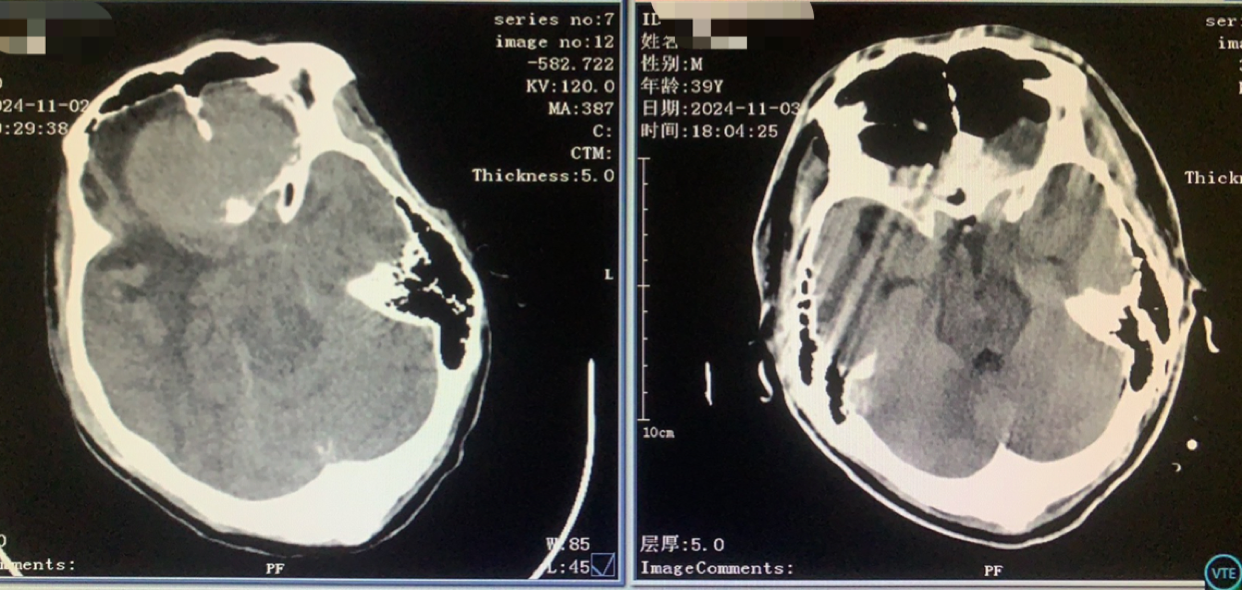

术前CT

神志昏迷双瞳散大对光反射迟钝入院,入院后甘露醇脱水加地米静滴后患者神经功能有改善,能摸索定位,瞳孔反射改善。考虑占位大直接切除可能出血多,拟术前栓塞处理,但造影发现栓塞不易风险高后放弃栓塞。

术前术后对比